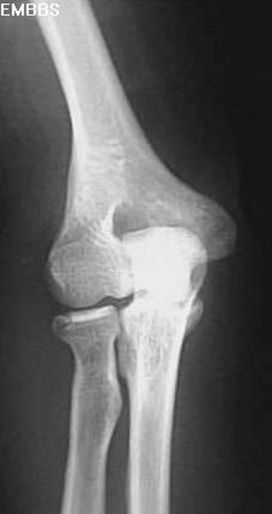

肱骨髁上骨折

肱骨髁间骨折

桡骨头骨折